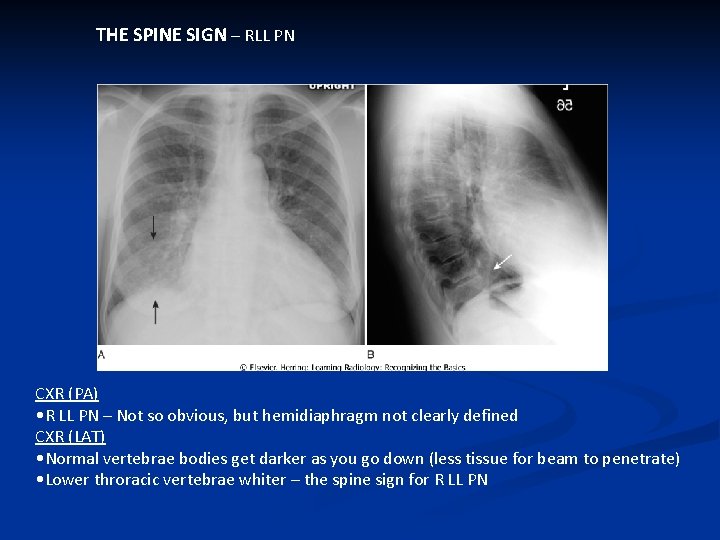

THE SPINE SIGN – RLL PN CXR (PA) • R LL PN – Not so obvious, but hemidiaphragm not clearly defined CXR (LAT) • Normal vertebrae bodies get darker as you go down (less tissue for beam to penetrate) • Lower throracic vertebrae whiter – the spine sign for R LL PN